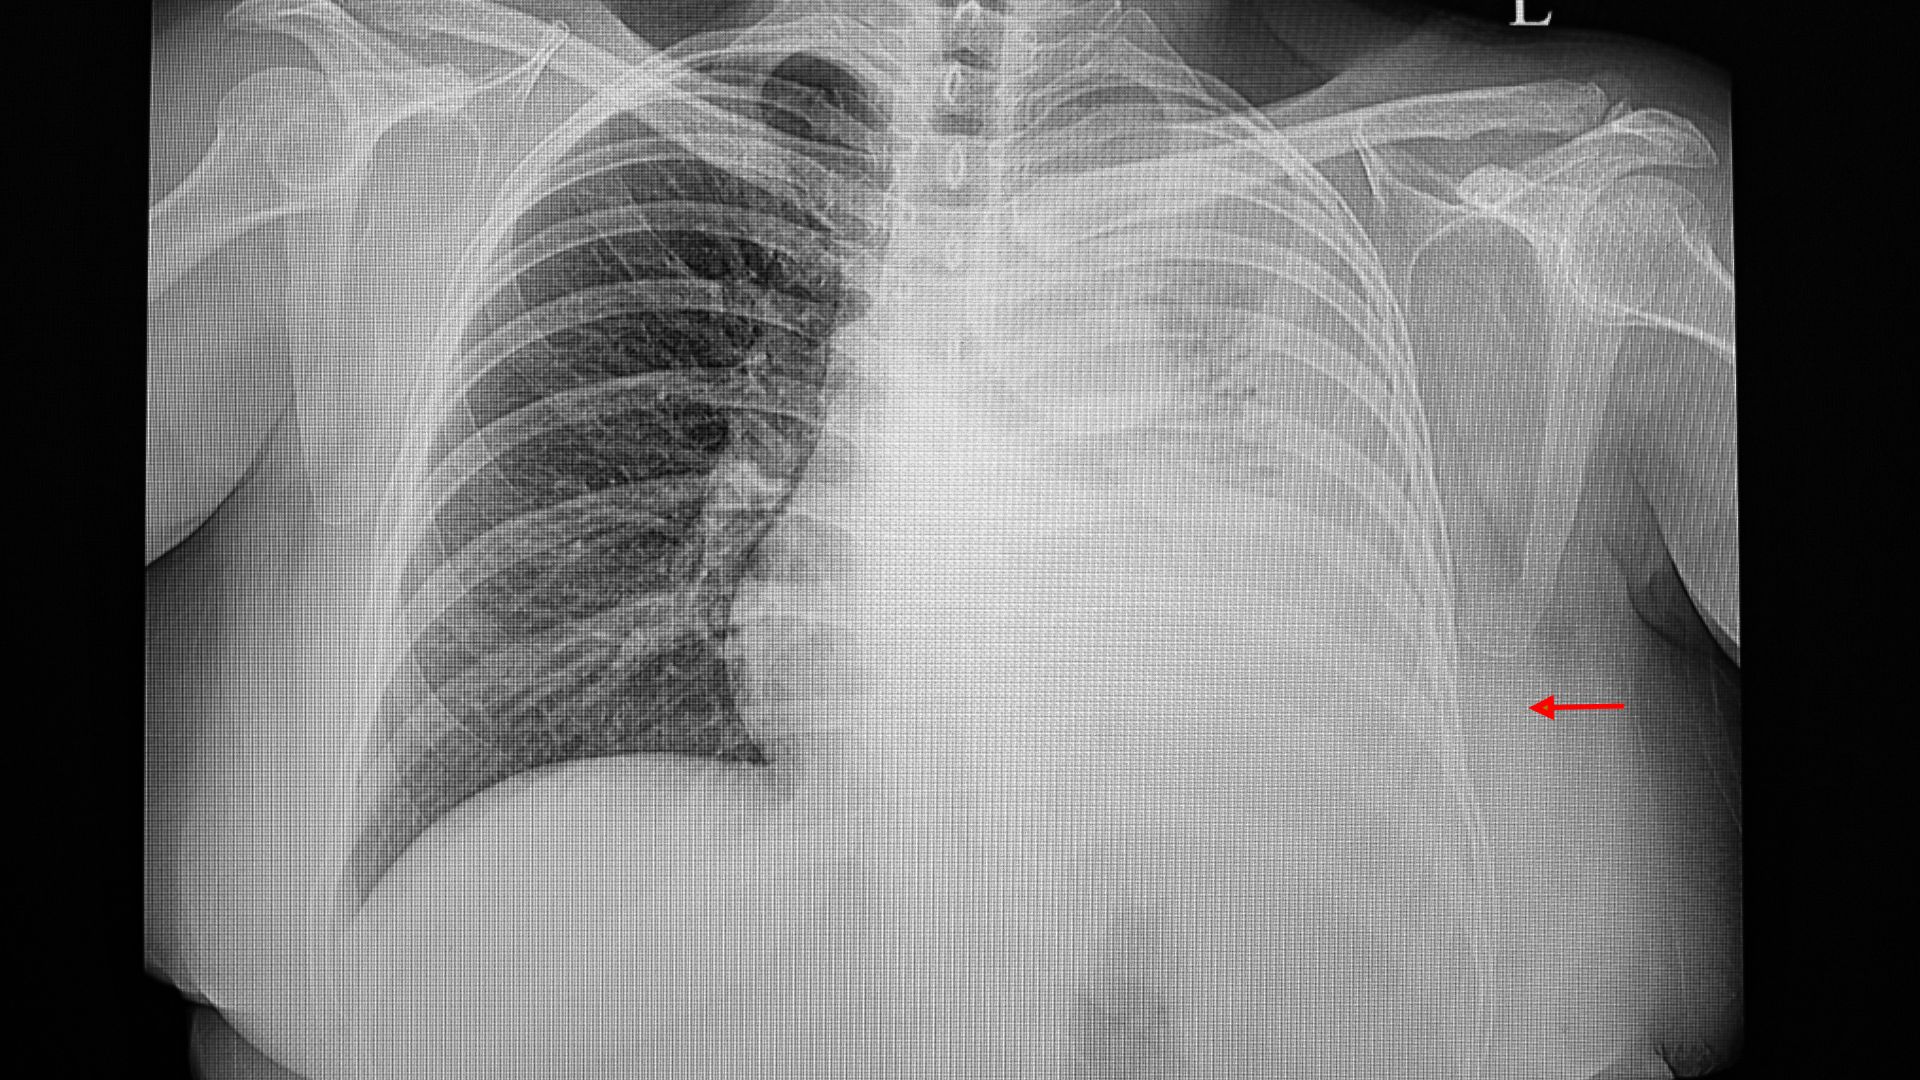

Khi bệnh bước sang giai đoạn tiến triển, hình ảnh phổi cho thấy những thay đổi rõ ràng hơn. Khối u tăng kích thước, ranh giới trở nên không đều và bắt đầu chèn ép các cấu trúc xung quanh như phế quản hoặc mạch máu. Các vùng phổi lân cận có thể xuất hiện hình ảnh xẹp phổi hoặc viêm do tắc nghẽn đường thở.

Ở giai đoạn này, người bệnh thường bắt đầu có triệu chứng rõ ràng hơn như ho kéo dài, khó thở hoặc đau ngực. Hình ảnh y khoa phản ánh mối liên hệ trực tiếp giữa tổn thương giải phẫu và biểu hiện lâm sàng, cho thấy bệnh đã ảnh hưởng đáng kể đến chức năng hô hấp.